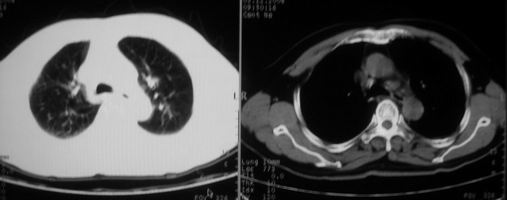

抗炎治疗一周热退,提示为炎症,现片示病灶范围增大,边缘清楚,建议继续治疗,不除外肺脓肿

炎症性病变;左侧胸腔积液。

ct左肺下叶大片状高密度影,病变密度不均,界限不清,左侧胸腔积液,治疗后复查临床症状好转而影像学表现病变有发展,还是首先考虑感染性病变,复查时间短附合感染性病变的病理改变。

两肺炎症感染(以左肺下叶为著),双侧少量胸腔积液;建议继续抗炎治疗。